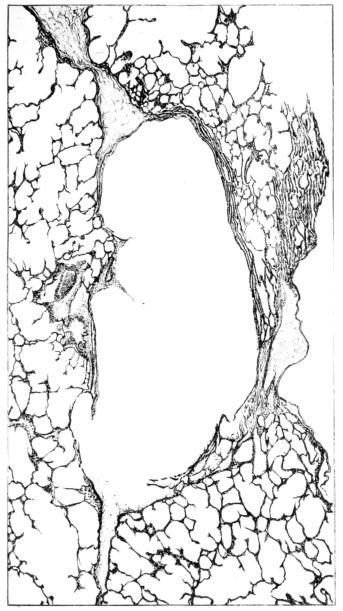

FIG. I. AUTOPSY NO. 99. ACUTE HEMORRHAGIC AND ULCERATIVE LARYNGOTRACHEITIS.

FIG. I. AUTOPSY NO. 99. ACUTE HEMORRHAGIC AND ULCERATIVE LARYNGOTRACHEITIS.

Early in the disease the congestion and the hemorrhages that have been described in the mucous membrane of the nasopharynx (14 and 94) are also conspicuous features in the lining of the trachea and bronchi (Fig. I). This membrane is swollen, turgid, red, and covered by a copious, mucous exudate which may be clear, but much more frequently is blood-stained or opaque and yellowish in color. The blood, variable in amount, may be fresh and red; and after the mucous exudate on the surface is removed, more intense red foci stand out on the congested base (47, 90, 157). Frequently, as the bronchi are approached, the red color of the mucosa becomes more intense and may have a garnet tinge. Membranes such as are encountered in the more usual necrotizing inflammatory processes, like diphtheria, have not occurred in the trachea and larger bronchi in this series (108, 128, 157).[3] The exudate peels off readily, and as indicated above, leaves a velvety red surface, 14dotted here and there with darker or more intensely red foci. Small ulcerations of the mucosa occur, but are inconspicuous (82, 156). As the finer ramifications of the bronchi are approached, the accumulation of the exudate in their lumina becomes more and more marked, and on cross section of the lung, they often stand out conspicuously on account of their increased size and projecting, seromucous, blood-stained content (101, 149, 162).